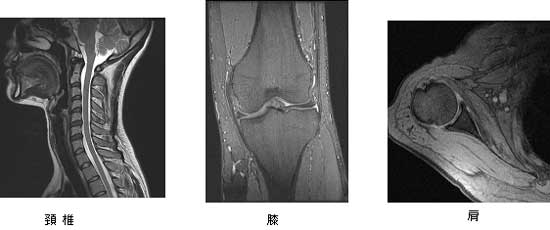

整形外科領域

脊椎領域では、椎間板ヘルニアや脊柱管狭窄症における神経圧迫の程度が鮮明に描出できます。

また、造影剤を使用せずに脊髄造影像と同様な画像を構成することが可能です。

その他の整形外科領域において、一般的にX線にて評価の困難とされる筋肉や靭帯、軟骨などの評価にも有用で四肢や股関節などの関節疾患、腫瘍性病変の検索、評価と使い方は多種多様です。